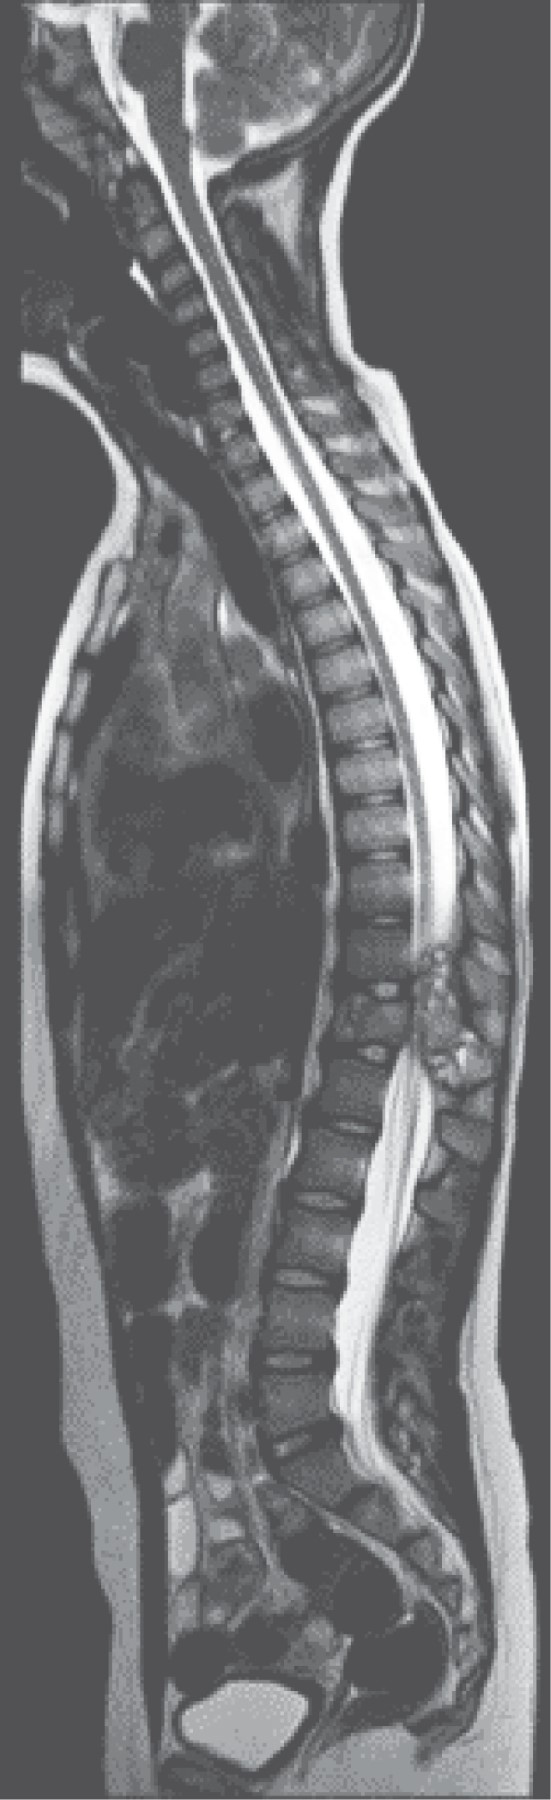

La RM simple y contrastada caracterizó de mejor forma lesión, siendo extradural, heterogénea, con una porción multilocular con niveles líquido-líquido observados hiperintensos en T2; presentaba también una porción sólida que realzaba al contraste, la cual invadía al canal medular generando invasión anteriormente hacia el cuerpo vertebral, con destrucción del pedículo, proceso transverso y la lámina (Figuras 2, 3, 4, 5 y 6).